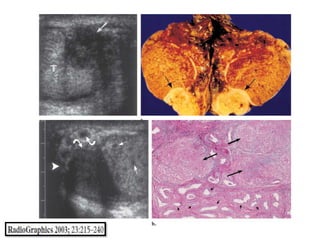

Epidídimo

La principal vía de infección del epidídimo es la

diseminación hematógena, así como la siembra

retrógrada desde la próstata a través del conducto

deferente.

Clínicamente, los pacientes pueden presentar

inflamación del escroto, dolor e incluso

secreción. Algunos pacientes también pueden

presentar síntomas irritativos del tracto urinario

inferior.

Debido a que las lesiones suelen ser unilaterales,

pueden ser difíciles de diferenciar de otras masas

benignas.

La tuberculosis se sospecha a menudo sólo después de

que los granulomas se encuentran en patología.

Testículo

La tuberculosis del testículo generalmente se

asocia con la infección del epidídimo. Infección

aislada del testículo sin afectación del epidídimo

es un evento muy raro.

Una masa testicular asociado a lesiones del

epidídimo es muy sugestiva de una lesión no

neoplásico.